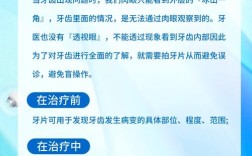

- 术前评估: 必须拍摄根尖片和曲面断层片评估牙根长度、牙槽骨高度、邻牙情况,必要时进行CBCT精确评估三维骨形态和牙根位置(尤其靠近重要解剖结构如神经管时)。牙周探诊深度、附着丧失、牙龈生物型(厚薄) 对手术设计和预后至关重要。